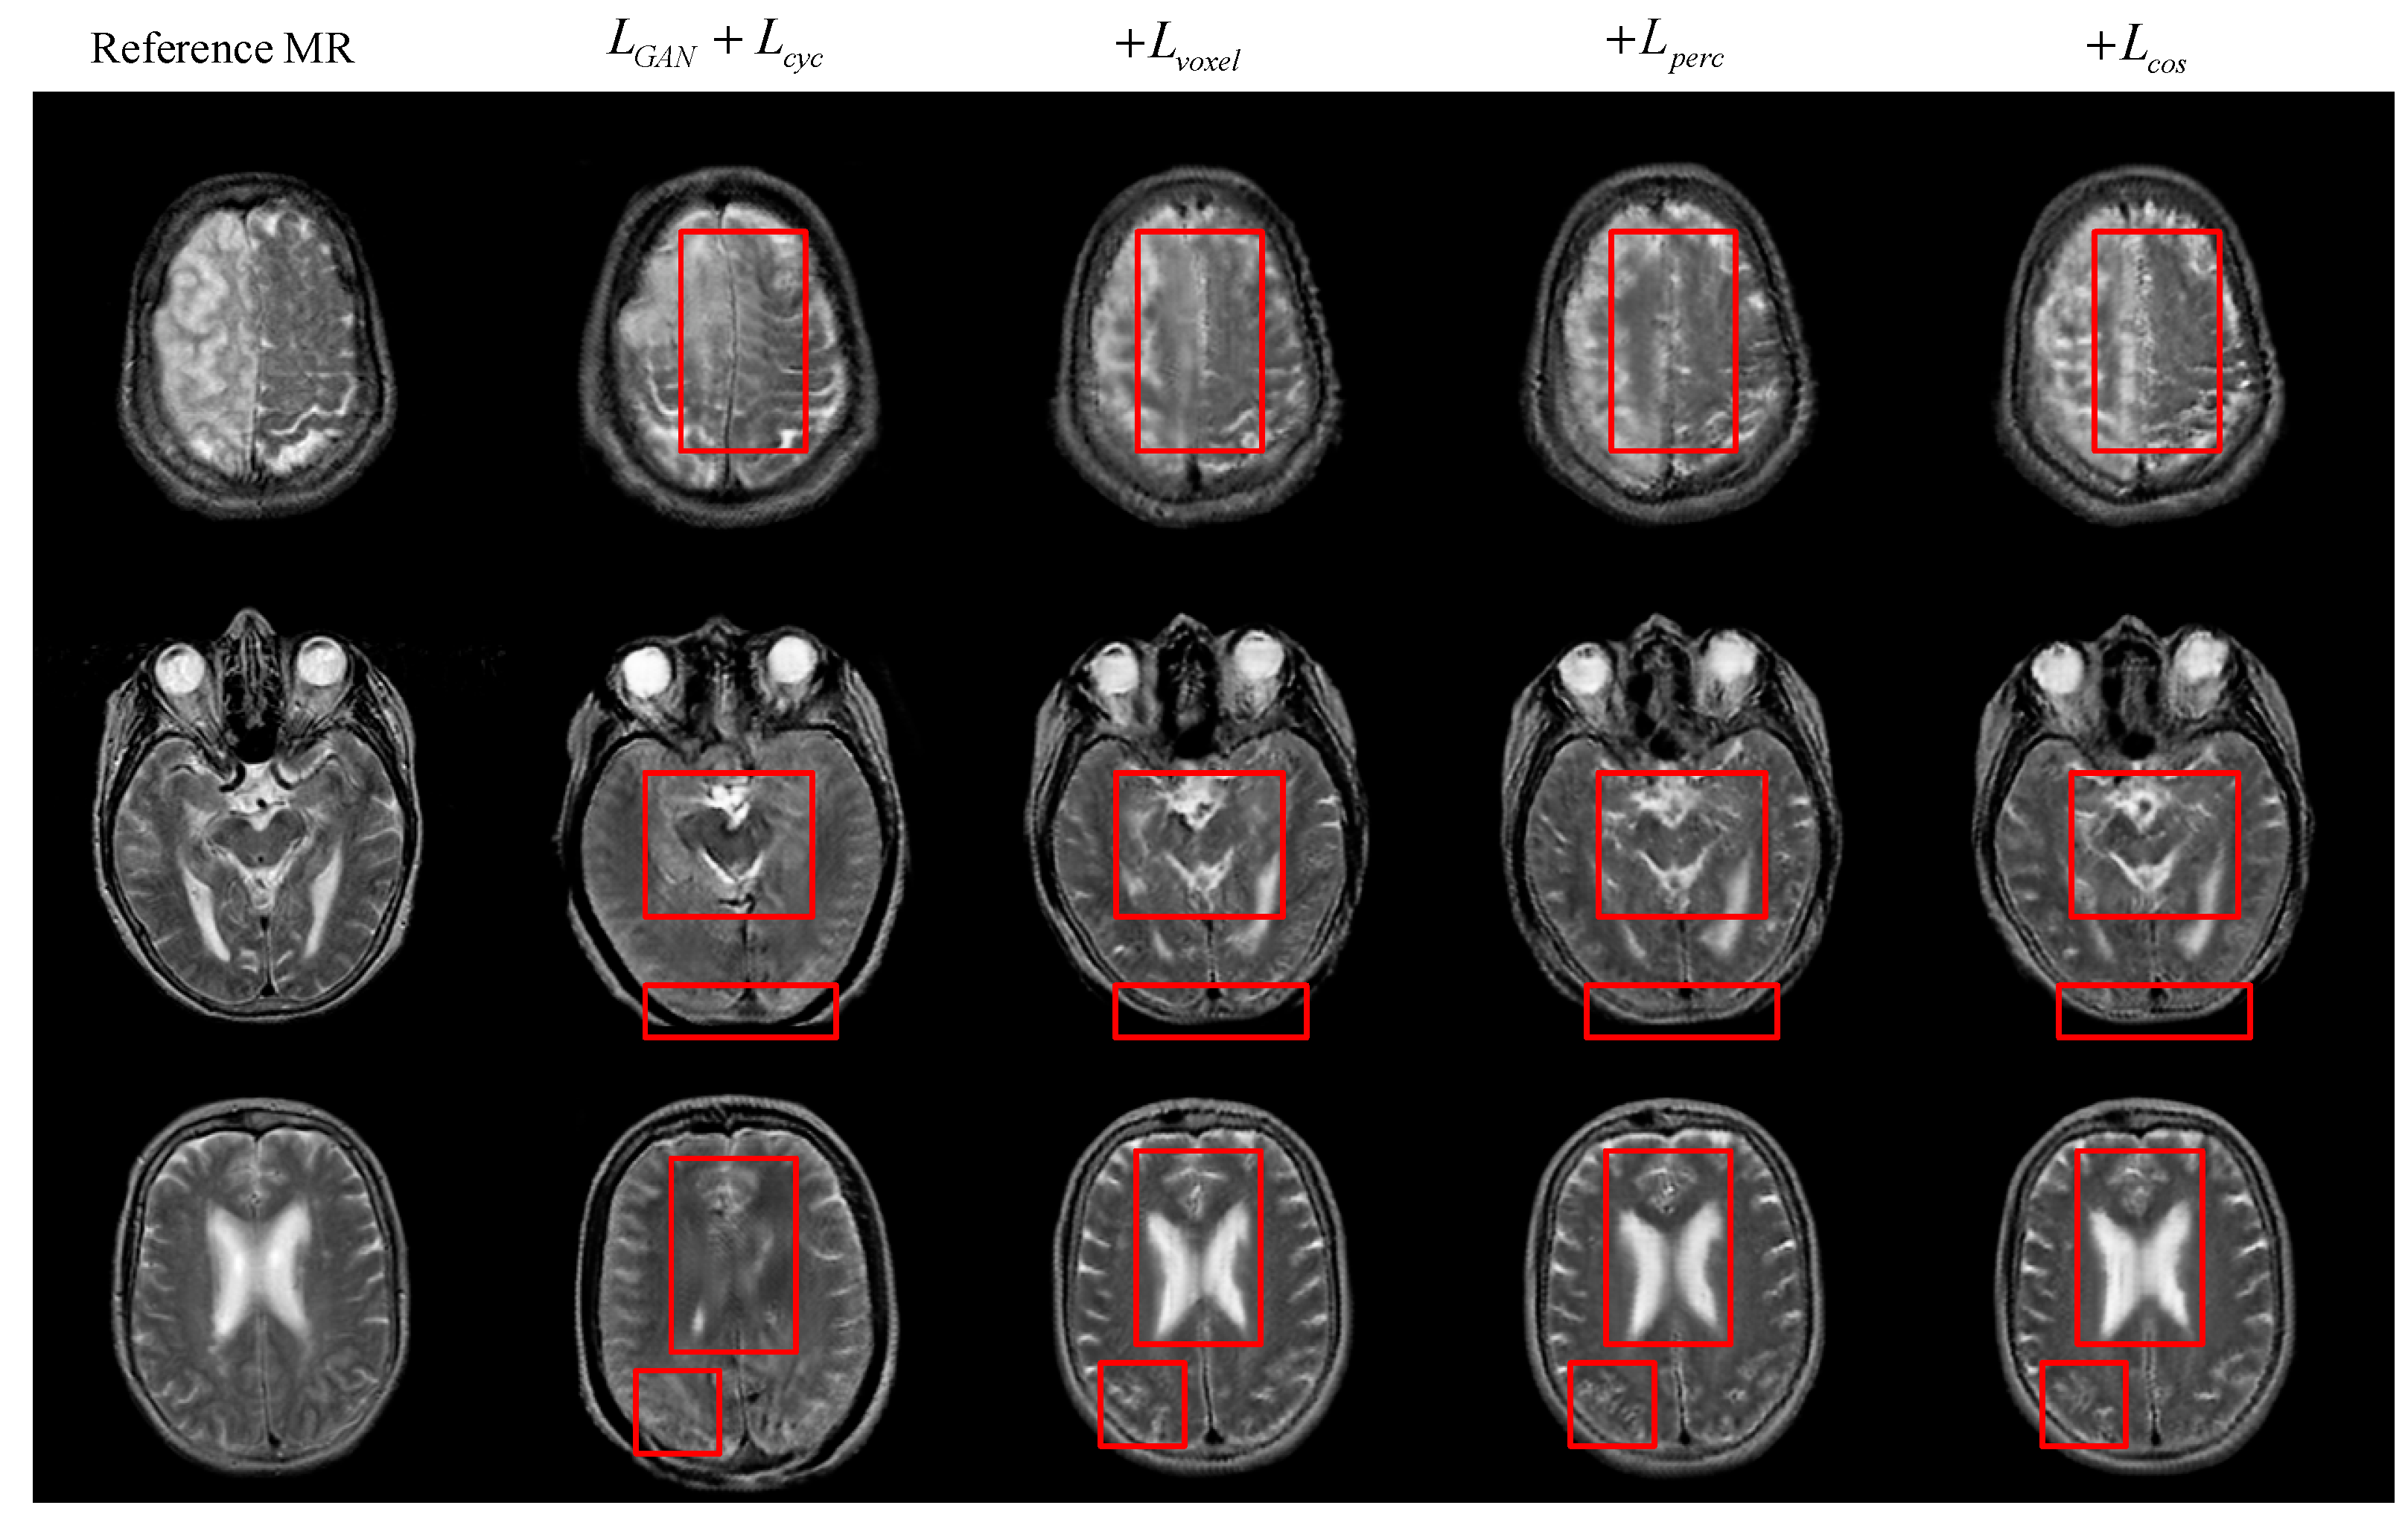

4.2. Comparison of Results under Different Objective Optimization Functions

| MAE ↓ | RMSE ↓ | PSNR ↑ | SSIM ↑ | PCC ↑ | |

|---|---|---|---|---|---|

| LGAN | 19.054 | 36.343 | 65.157 | 0.52 | 0.761 |

| +Lvoxel | 13.163 | 25.844 | 68.423 | 0.647 | 0.869 |

| +Lperc | 13.141 | 25.636 | 68.476 | 0.645 | 0.87 |

| +Lcos | 12.981 | 25.532 | 68.519 | 0.652 | 0.872 |